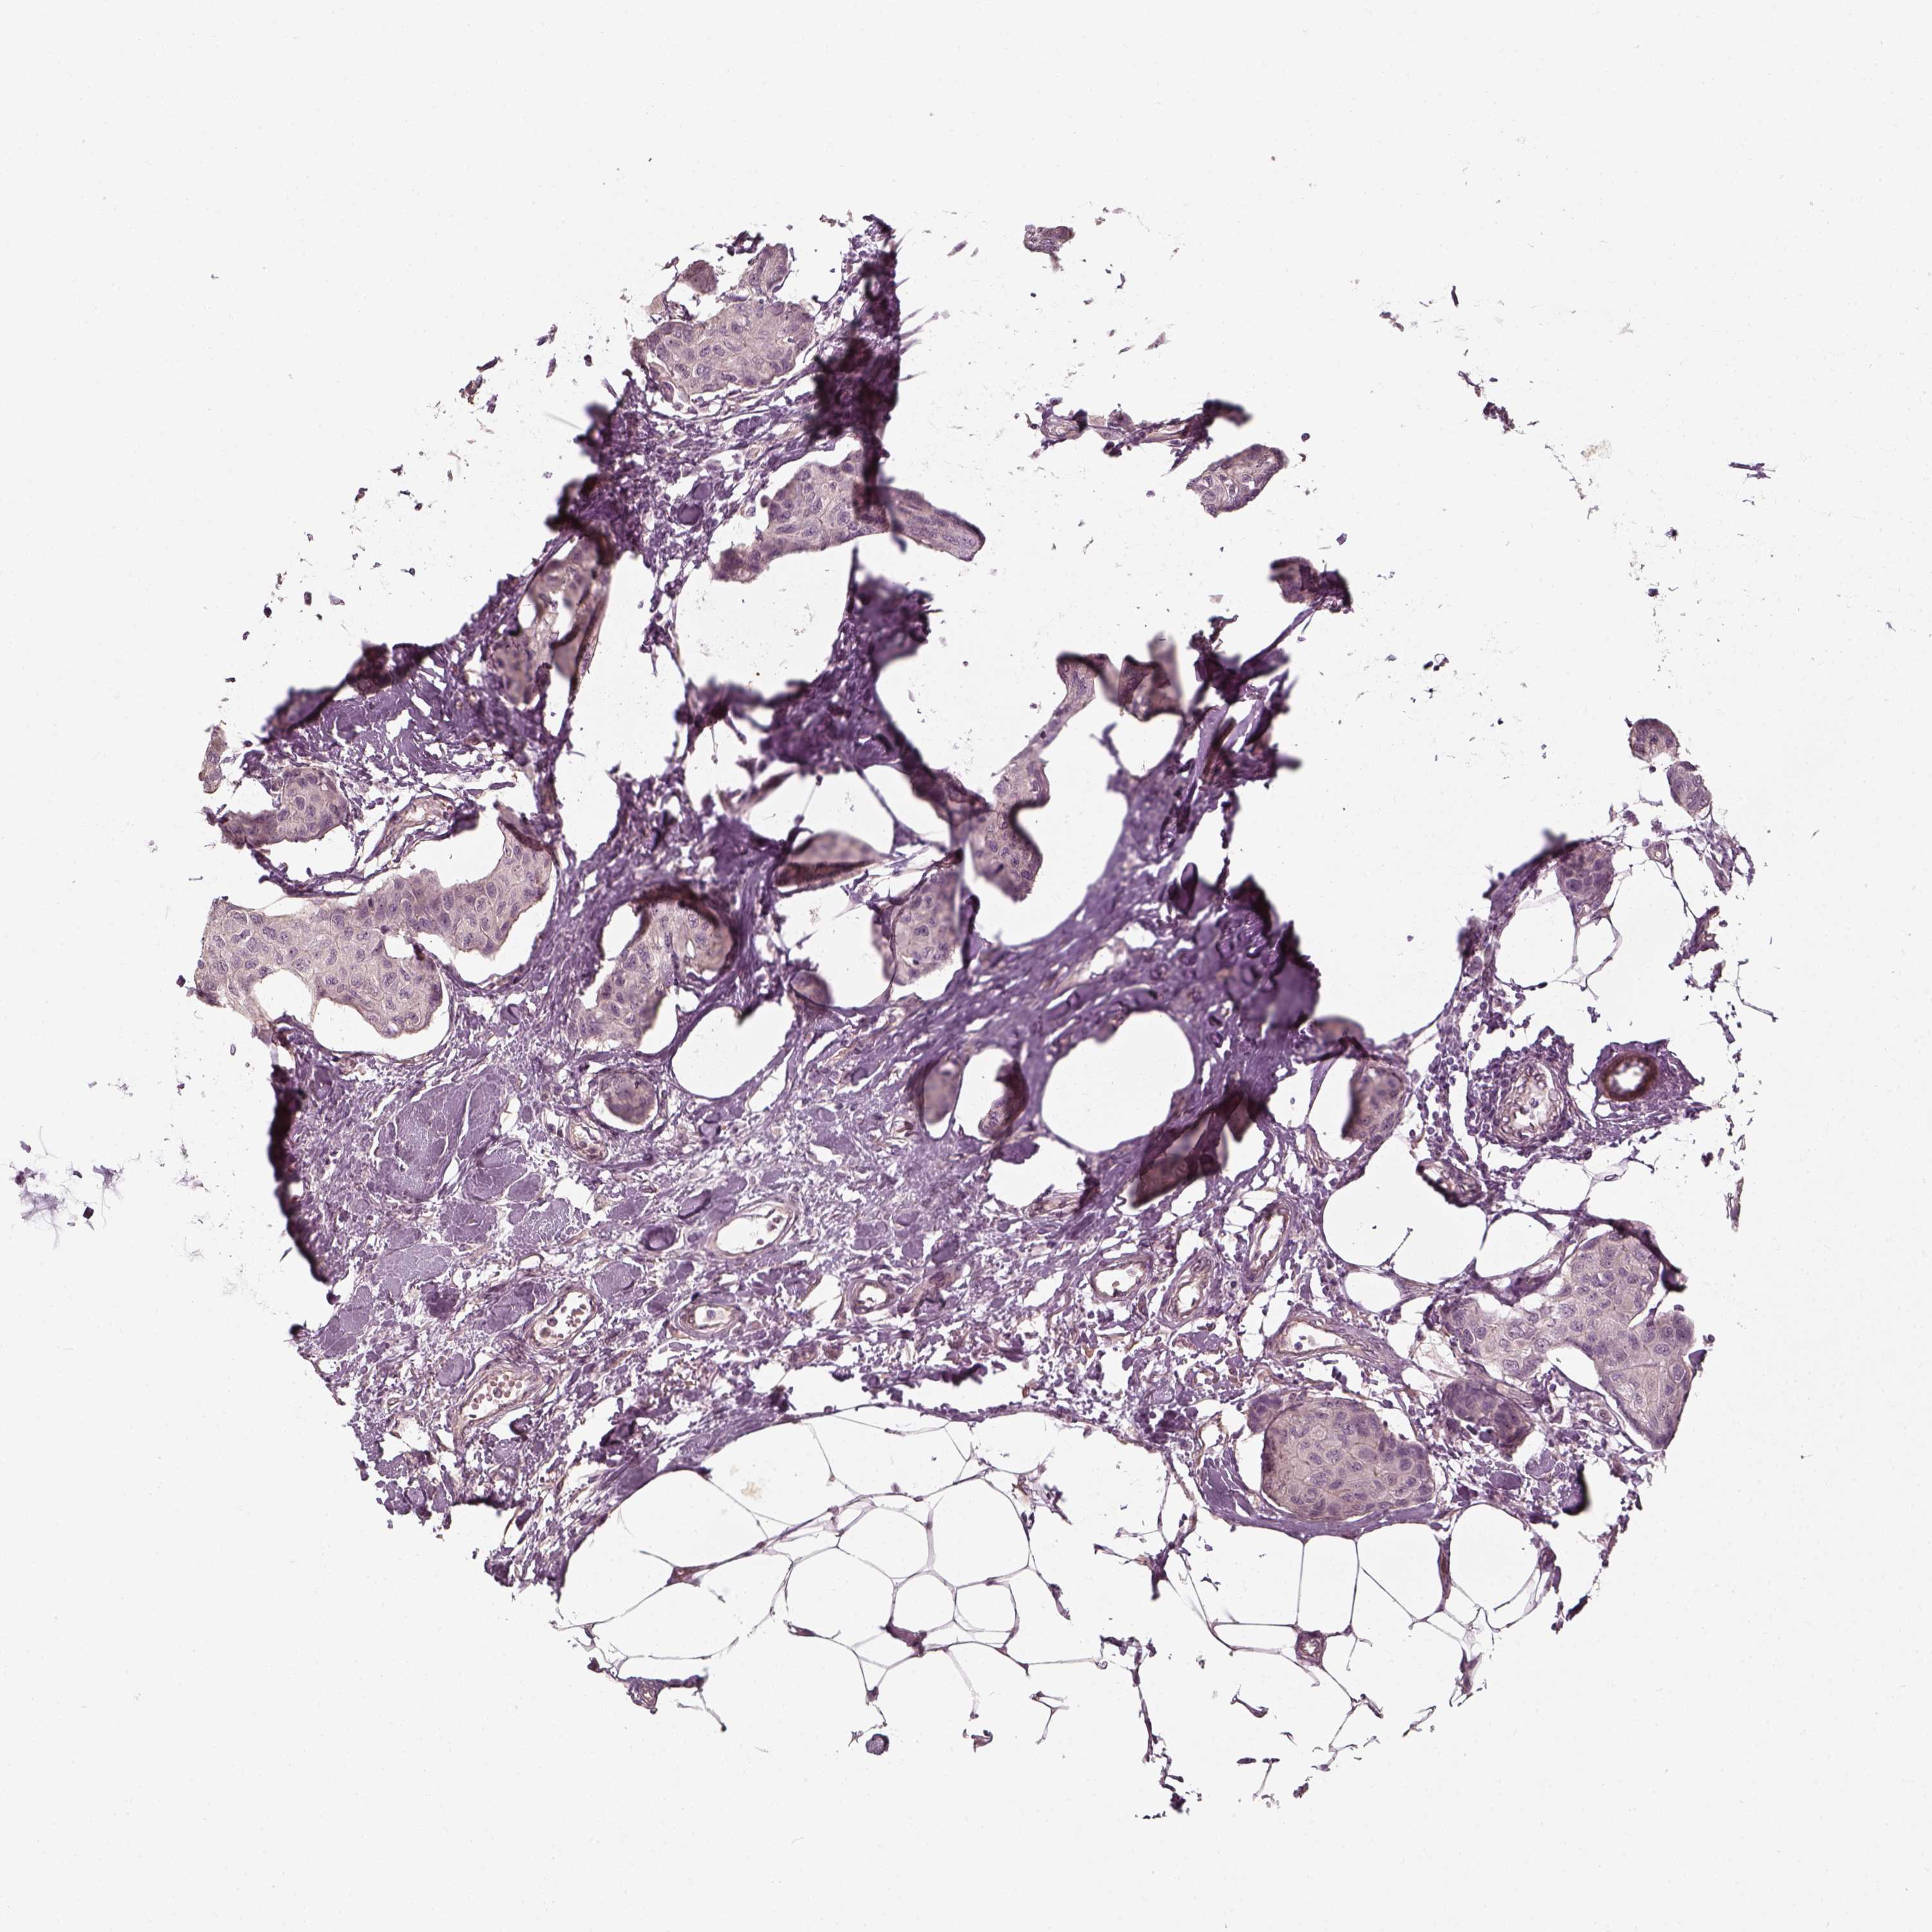

CANCER BREAST CANCER Show tissue menu

BRCA TCGA BRCA VALIDATION PROTEIN EXPRESSION

Breast cancer

Human cancer